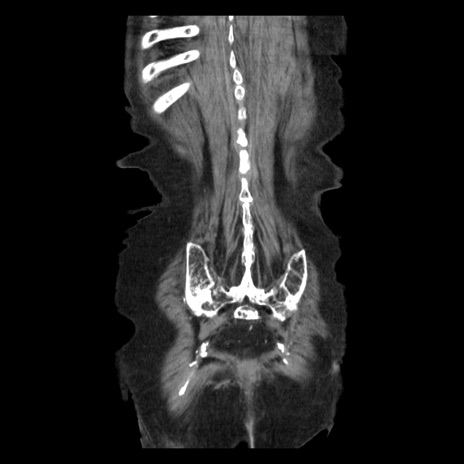

症例14(冠状断像)

【症例】 90歳代女性

【主訴】 腹痛・嘔吐

【現病歴】今朝から左側腹部痛を認めた。 経過観察していたが、嘔吐を認めたため来院。

【既往歴】 子宮癌術後

【身体所見】 意識清明、BP 127/54mmHg、P 98bpm Sp02 95%(RA)、BT 35.8°C、腹部平坦・軟腸ぜん動音聴取良好、右下腹部圧痛(+) 反跳痛なし

【データ】WBC 9800、CRP 0.46